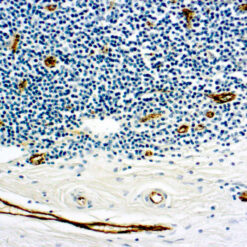

CD7 is expressed by most peripheral blood T cells, NK cells, and all thymocytes. It is one of the earliest surface antigens on T and NK-cell lineages. The antibody is a useful aid for classification of T-cell malignancies.

| Cellular Localization | Cell surface/membrane |

| Positive Control Tissue | Tonsil |